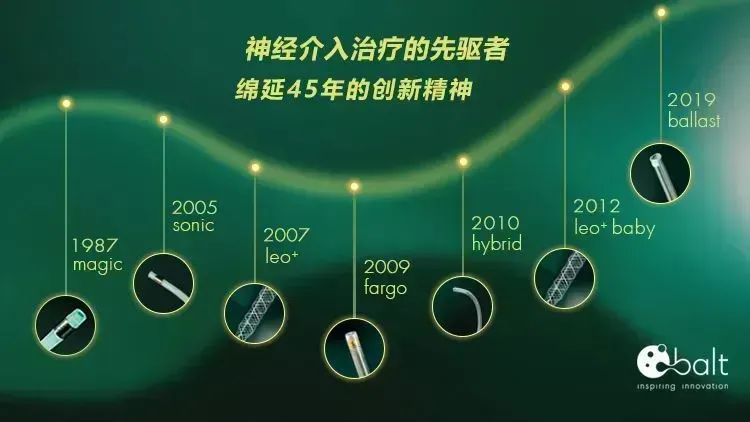

选择一枚LEO Baby支架 2.5*18mm辅助栓塞。

LEO+Baby支架 2.5*18mm